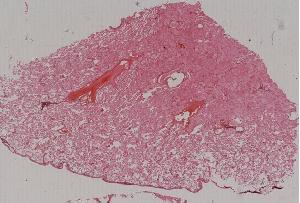

12. Acute pulmonary congestion